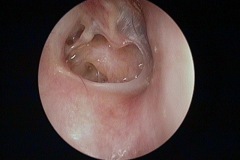

Atelectasis/Retraction

Perforation

Tympanic Membrane